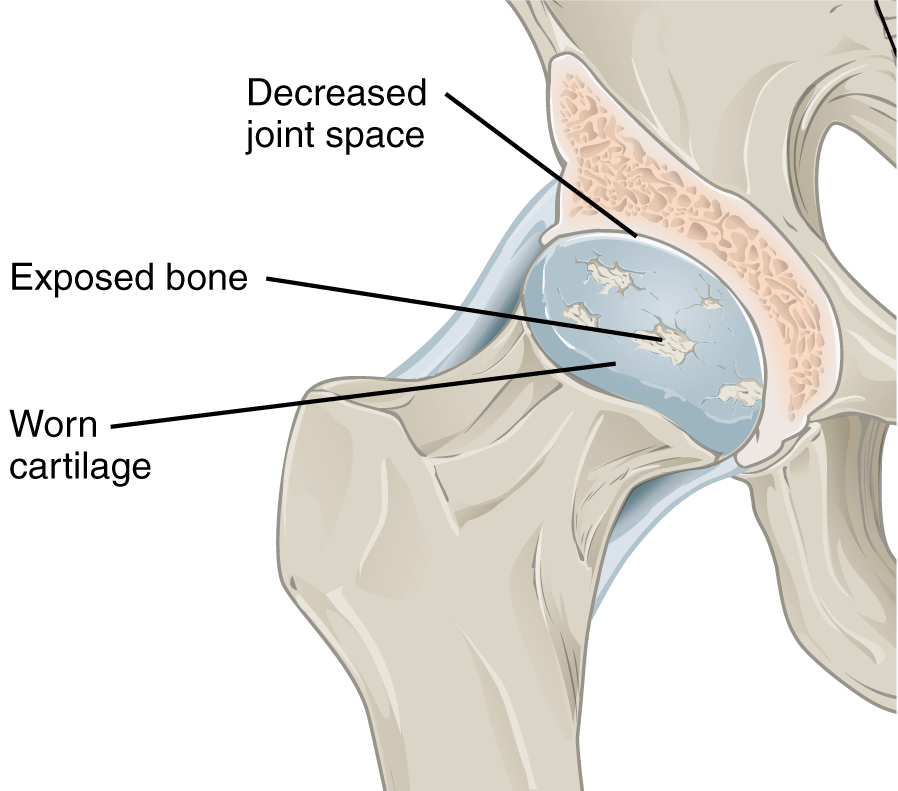

Детальная иллюстрация артроза тазобедренного сустава: хрящ и остеофиты Источник: Wikimedia Commons / CFCF, CC BY-SA 4.0

По методу Смирнова, остеопатия при артрозе коленного сустава редко начинается с самого колена. Коленный сустав почти никогда не является первичным источником боли (кроме случаев прямой свежей травмы) — он страдает как «заложник» компенсации.